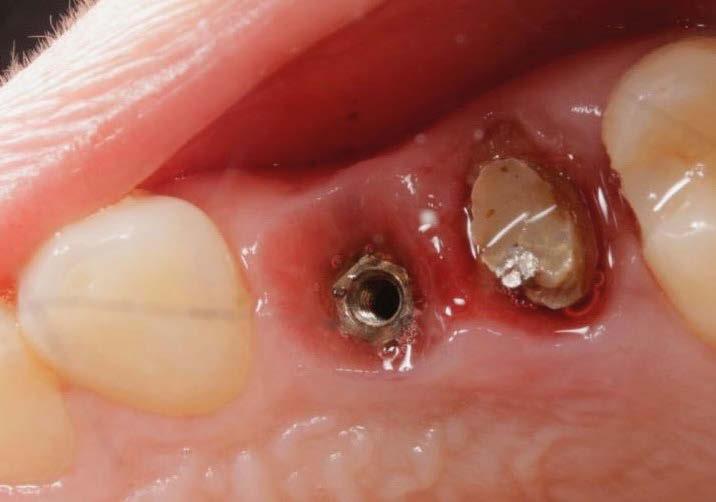

Para ilustrar el proceso, presentamos el caso de una mujer joven diagnosticada de carcinoma adenoide quístico en la región posterior del hemipaladar izquierdo (Figuras 1 y 2). El procedimiento quirúrgico realizado fue una

maxilectomía parcial que incluyó las piezas 24-26 y desde el reborde alveolar hasta la base del cráneo (Figuras 3 y 4). En este caso, la órbita y el globo ocular pudieron ser preservados. La reconstrucción inmediata se realizó mediante un colgajo de músculo temporal homolateral (Figura 5) y el defecto de la fosa temporal fue cubierto mediante una malla de titanio. Posteriormente, la paciente recibió radioterapia (Figuras 6 y 7). 2 años más tarde se diseñó un IS con anclaje en el arbotante nasomaxilar, zona subnasal izquierda

Figura 1. Imagen preoperatoria de la paciente.

Figura 2. Carcinoma adenoide quístico en región posterior del hemimaxilar izquierdo.

Figura 3. Maxilectomía parcial.

Figura 4. Defecto maxilar tras resección del tumor.

y lo que se pudo preservar del hueso malar. Se añadió una malla sinterizada infraorbitaria para dar volumen a la mejilla y se planificaron dos brazos de conexión que emergieran en las posiciones 24 y 26 de forma subgingival (Figuras 8 y 9). La superficie interna que apoyaba en el hueso era de titanio microrrugoso, y la superficie externa y conectores de titanio pulido y hexágono externo universal (Figuras 10 y 11). La cirugía se hizo bajo anestesia general en infiltración con anestesia local (4% articaína, 1:100.00 epinefrina), levantando el

colgajo cutáneo de la mejilla por vía intraoral, preservando el colgajo temporal para no comunicar con el remanente de la cavidad naso maxilar (Figura 12). Se emplearon 10 tornillos de osteosíntesis de 1,9 mm y la estabilidad primaria obtenida fue excelente (Figura 13)

4 meses después de la cirugía la encía estaba completamente cicatrizada y las conexiones de los implantes tipo hexágono externo universal quedaron a nivel yuxtamucoso. En este caso no se requirió el empleo de pilares transepiteliales y las impresiones fueron tomadas